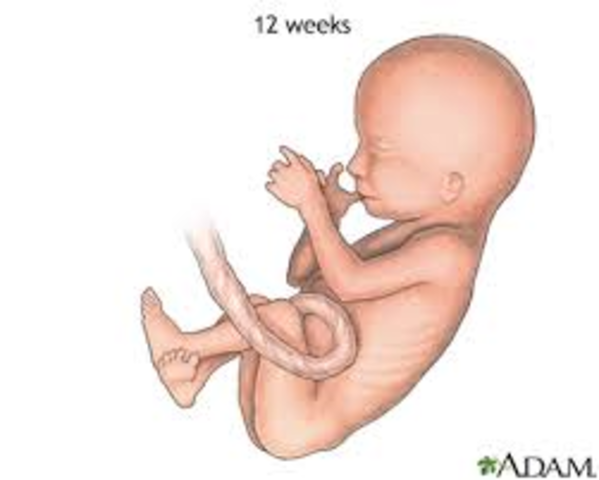

• Week Twelve

Week Twelve

The baby's brain and heart are fully formed, and the baby can also feel pain. Fingernails and toenails appear.